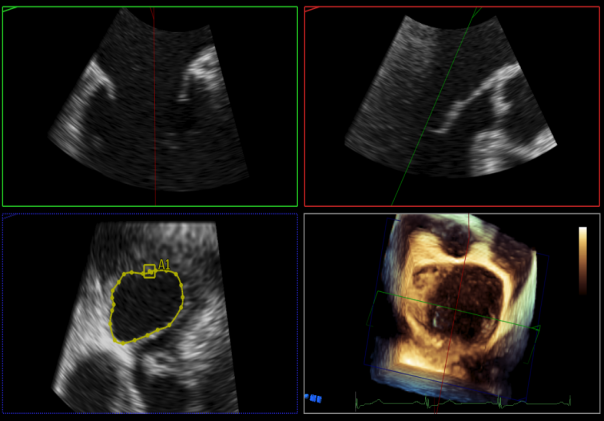

术中超声

P2区脱垂,宽14.8mm,Gap:3.3mm

3D-color,返流重度,3+级

麻醉状态下左肺静脉血流频谱

MVA:6.67cm²

房间隔穿刺点选择

穿刺高度:4.3cm